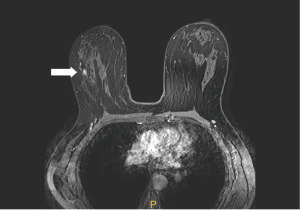

Figure 11 Mammography of the right breast in medio-lateral-oblique (A) and cranio-caudal view (B) with multiple densities with irregular margins and architectural distortions (arrows). Ultrasound (C) shows more than two hypoechoic lesions of suspicious features. In MRI (D) an extensive area of tumour involvement is revealed. MRI, magnetic resonance imaging. - A patient of 50 years of age evaluated for enlarged lymph nodes in the axilla. Mammography and ultrasound show enlarged pathological lymph nodes in the axilla, otherwise no pathological finding in the breast on initial evaluation despite the low mammographic density. The largest lymph node is biopsied proving metastatic invasive carcinoma NST of breast origin. MRI is indicated to search for an occult lesion in the breast. MRI shows the enlarged lymph nodes and a small lesion in the right breast in upper outer quadrant. A second-look, targeted ultrasound with the knowledge of the location of the lesion is performed to reveal a small suspicious lesion, which is subsequently verified as the primary tumour in the breast (Figure 12).

Figure 12 Enlarged lymph node in the right axilla is seen in mammography (A). In MRI (B) enlarged lymph nodes (star) are confirmed and a small mass with early intense enhancement in the upper outer quadrant (arrow). In ultrasound (C) the lesion is very subtle (arrow). MRI, magnetic resonance imaging. - Preoperative marking. Microcalcification with ductal distribution biopsied by vacuum—assisted biopsy under mammography guidance as DCIS grade 2; the extent of the calcifications is approximately 30 mm. Marking by two wires is performed to delineate the extent of the disease. A specimen mammography of the resected tissue shows both wires with microcalcifications between them that do not reach the margins (Figure 13).